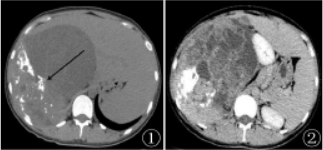

患者女,20岁。5个月前因进食后右上腹胀,无腹痛,当地市医院就诊。超声检查:显示“肝脏下方囊实性肿块,建议进一步检查”而就诊我院,实验室检查:糖类抗原125(CA125)45.66U/ml。

图1

腹膜后UPS的CT表现:大部分肿瘤形态呈类圆形软组织肿块影,直径多>5cm,平扫多呈混杂密度,常见低密度囊变坏死区,肿瘤的坏死程度与病变的大小呈正比,钙化少见,肿瘤强化大部分呈不均匀中度或明显强化;MRI相对于CT具有能较好地显示病变边界、范围以及与周边组织关系的优点。